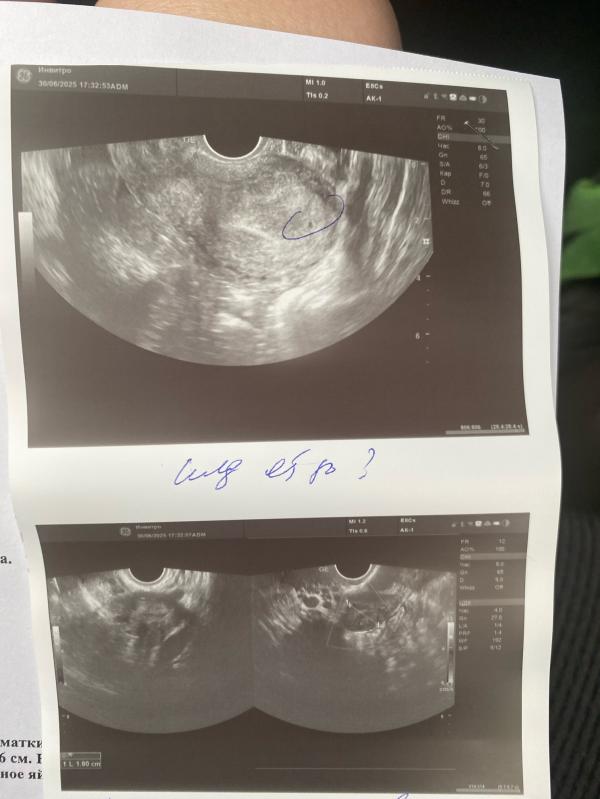

Сегодня была у врача , хгч 1006 сказали плодное яйцо в матке , срок 2-3 недели где-то. Сказали хгч смотреть и там еще все все очень маленькое. Но мне сказали посмотреть хгч через 7 дней.

@love453010, сегодня узи было и через неделю еще узи переделать , сказали да от 1000 это хороший результат. А хгч когда вам повторно сдавать ?

Здравствуйте, мой врач сказала от 1000. У меня где-то так и нашли, а сначала пришла слишком рано хгч было около 600 и не увидели, сказали прийти через пару дней

Не знаю сколько хгч. Я не сдавала. 4.6 по месячным - 3.5 мм пя

Пя было 8,7 мм

Хгч не знаю сколько был. Ходила в 4.6 по месячным было пя 6мм и жм.